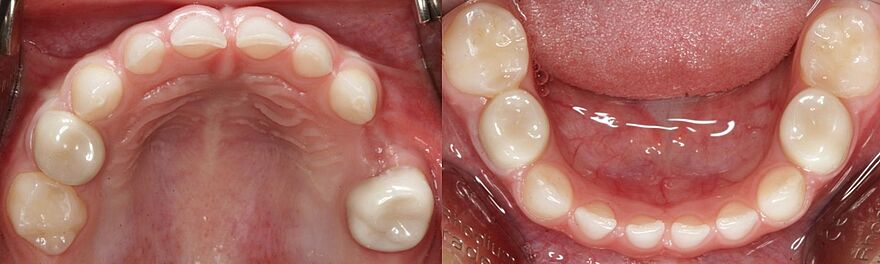

Dieses Milchgebiss wurde fachgerecht saniert. Die Karies ist verschwunden. Die Milchzähne werden erhalten, bis sie von den bleibenden Zähnen ersetzt werden. Dafür wurden auch Milchzahnkronen eingesetzt. Jetzt sind beste Bedingungen für eine effiziente Prophylaxe gegeben.